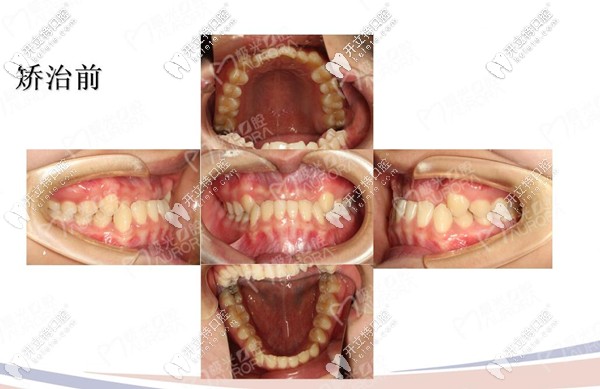

戴牙套之前的樣子

地包天矯正前后對比圖